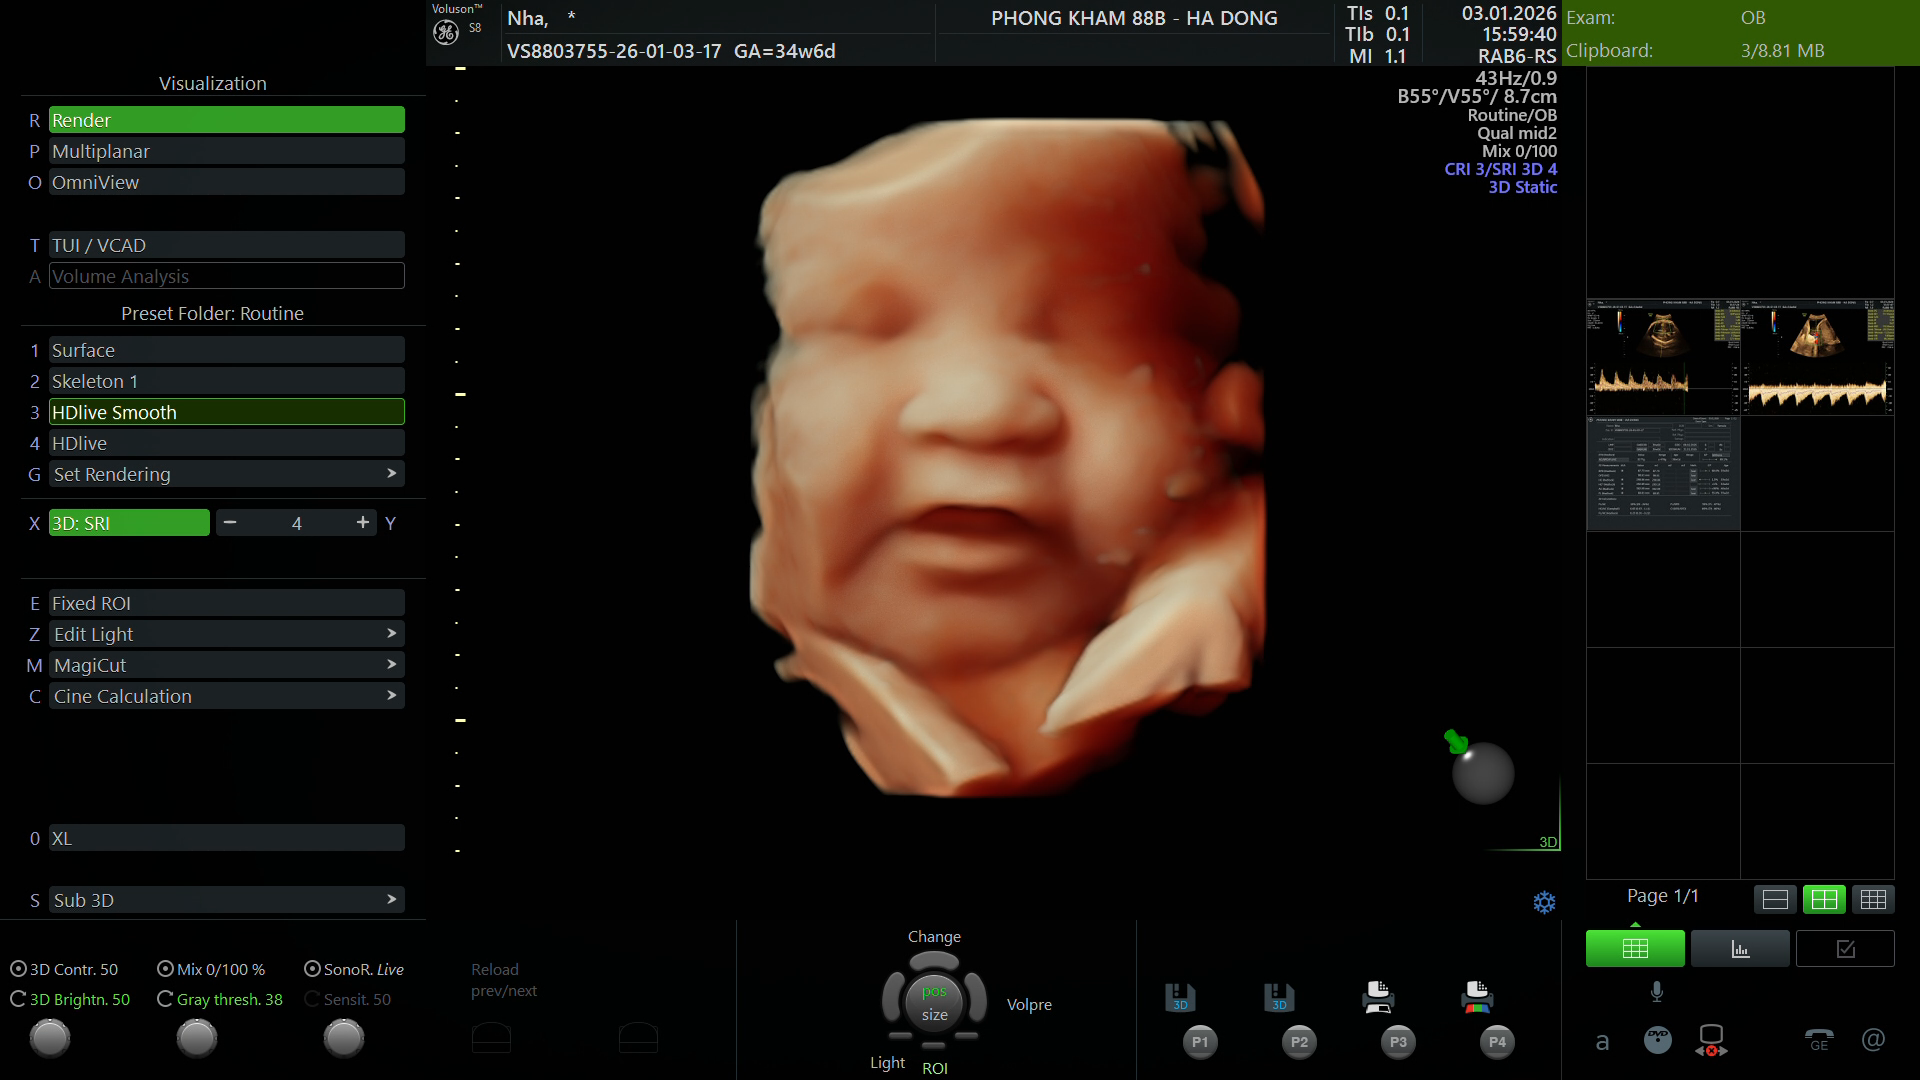

Phòng khám Sản phụ khoa 88B chúc mừng mẹ Ngô Thị Thanh Nhã đã hoàn thành buổi thăm khám và siêu âm định kỳ vào ngày 3/1/2026.

Dưới đây là hồ sơ kết quả siêu âm chi tiết được thực hiện và trực tiếp phân tích bởi Bác sĩ Nguyễn Dương Diệp

Phiếu kết quả siêu âm

(Mẹ vui lòng xem chi tiết các chỉ số sinh học và đánh giá hình thái thai nhi trong ảnh dưới đây)